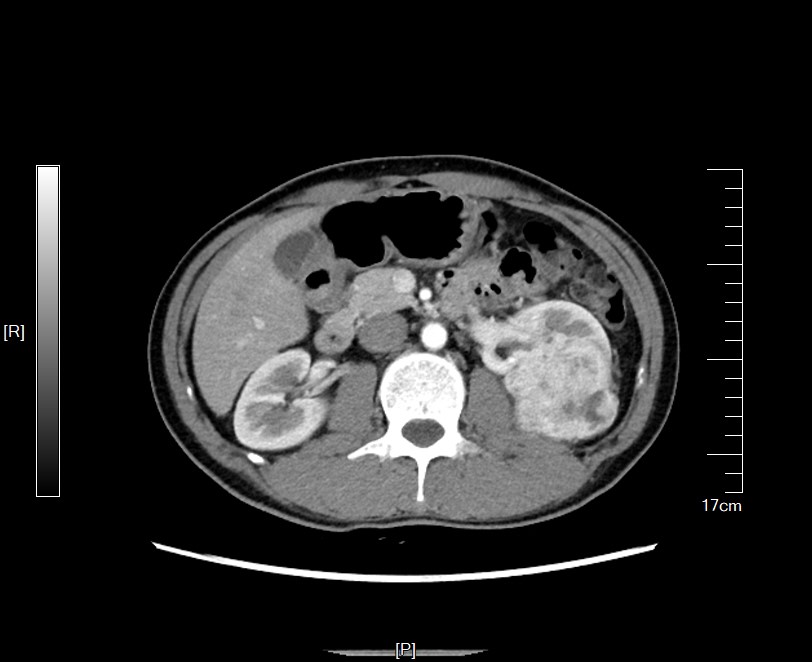

周先生住院进行了CT检查,发现在左侧肾脏上长了一个巨大的肿瘤,大约有7cm大小,占到了肾脏半数以上的体积。